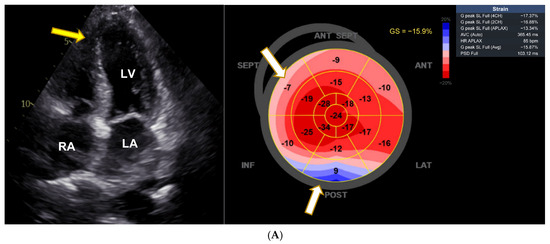

There was normal systolic and diastolic function, normal renin, aldosterone, adrenalin, and noradrenaline levels measured in serum, methoxytyramine was massively elevated (309 nmol/mL, normal range 0.59–4.19), and MRI showed no kidney or adrenal abnormalities. Echocardiography revealed signs of apical hypertrophic cardiomyopathy and decrease in global longitudinal strain (GLS) to −15.9% (Figure 1A). VEN serum concentration was not determined. VEN-associated CTOX was suspected and her migraine treatment switched from VEN to fremanezumab. Subsequently, within one year, the patient showed almost normal blood pressure values, normalization of ECG changes, and an increase in GLS to −21%. The echocardiographic signs of left ventricular hypertrophy had regressed (Figure 1B), and blood pressure had decreased to 143/84 mmHg. She had no dyspnea anymore, and her methoxytyramine levels had completely normalized.

Figure 1.

Pronounced cardiac anomaly showing features of hypertrophic cardiomyopathy. (A) Echocardiographic changes with apical hypertrophy and apical sparing pattern with decrease in strain in basal segments (white arrows). LA = left atrium, LV = left ventricle, RA = right atrium; white arrow points to left ventricular hypertrophy. Average GLS as shown on the right side is diminished and shows apical sparing (white arrows). (B) Reversal of left ventricular hypertrophy and apical sparing pattern after dose reduction of venlafaxine. LA = left atrium, LV = left ventricle, RA = right atrium; yellow arrow points to left ventricular hypertrophy. Average GLS as shown on the right side has now almost completely normalized (−21.9%), with some remaining decrease in basal septal, anteroseptal, and anterior segments (white arrows).